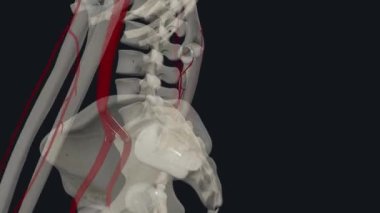

SağlıkkanİlaçkalpStetoskopTedaviHastalıkbiyolojiGöğüsorgİyileştiriyorvenanatomibelirtileriobstrüksiyonarterkapillerkasılmaAtriumGöğüs kemiğiaortKalp kriziKalp kasıGöğüs Ağrısıkalp zarınıKan damarıStentkan akımıacil tedaviKoroner artersol ventrikülSağ ventrikülkalp ilacıdiyaframdanKalp kapakçığıkardiyovasküler sistemSol atriyumPulmoner dolaşımSistemik dolaşımPulmoner arterSağ atriumsemilunar valvepulmoner venbicuspid valvepapillary musclecardiac septumcardiac wallheart catheterisationBenzer İçerikler